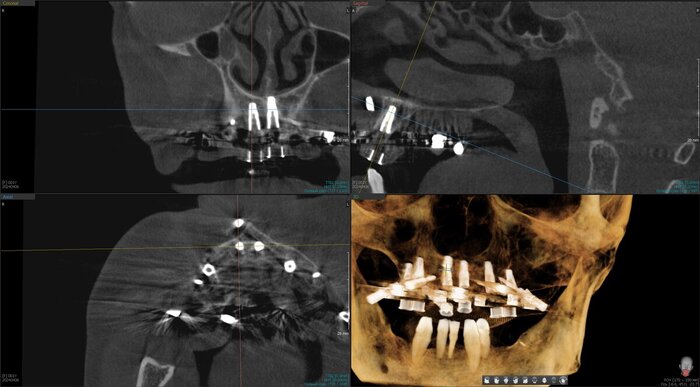

Получилось так, что сверху всего 8 зубов, по 4 с каждой стороны. Чёрная точка (которую вы точно увидите, скос эмали на зубе 1.1) - конструктивные особенности, всё это будет закрыто пломбировочным материалом. Зуб 1.1 - дополнительный имлантат, который потом планируем убрать. Он нужен лишь для усиления, ибо торк полноценный был получен только на одном из остальных 6-ти установленных.

Напоминаю - протезы временные адаптационные

Так же важный момент - верхний протез соприкасается с нижним только в точках полученного торка (их всего 2), остальное "на весу" и жевать не способно.

Рекомендации - мягкая, жидкая пища 4 месяца! Это важно.